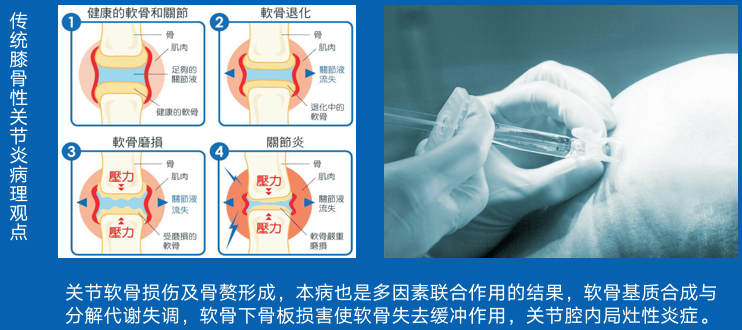

7、干细胞骨关节修复

国内治疗情况

中国骨关节炎患者的常规治疗包括口服消炎药止痛和氨基葡萄糖类药物、关节腔内注射玻璃酸钠、物理治疗和外科手术等,但效果并不理想。

美国骨科医师学会(AAOS)唯一推荐的骨关节炎治疗药物为非甾体类抗炎止痛药,然而该类药物却无法延缓关节软骨磨损和骨关节炎的进展。

干细胞修复原理

干细胞通过关书腔内注射,达到关节腔能够进行长期的自我复制,生长,分化,增殖,可以适应不规则的骨缺损及软骨缺损,促进半月板和骨体积增加,还可以加速不全撕裂的肌腱韧带的愈合,有效改善关节功能。

(多向分化,自我更新)

干细胞在不同分化发育阶段,细胞数量发生动态变化,分泌活性因子,促进细胞基质成分生成,并促进血管生成,改善关节腔内的微循环。

(分泌作用)

间接调节树突细胞和自然杀伤细胞,抑制T淋巴细胞的增殖,阻止T细胞反应,以及炎性细胞因子,减低了关节腔内局部微环境中免疫性细胞间的相互作用,促进炎性水肿吸收,从而改善症状。

(免疫调节功能)